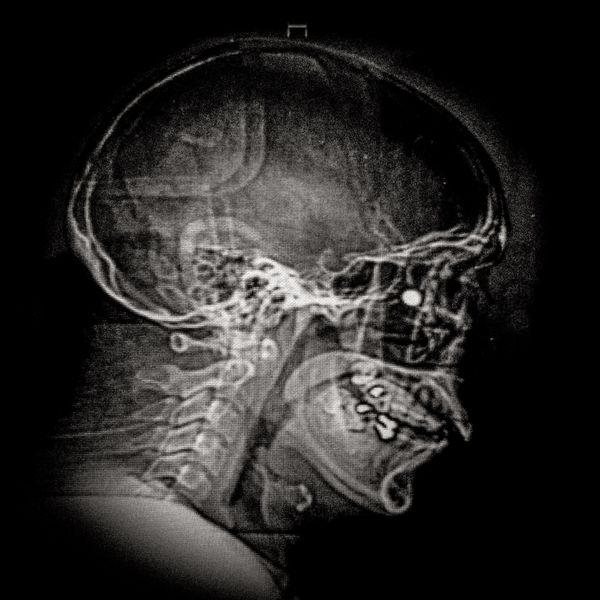

460 people have been seriously injured in their eyes, 34 of whom suffered total loss due to the indiscriminate use of pellets and tear gas bombs by the Carabineros de Chile special forces. The Carabin

460 people have been seriously injured in their eyes, 34 of whom suffered total loss due to the indiscriminate use of pellets and tear gas bombs by the Carabineros de Chile special forces. The Carabineros fired their rubber bullets and tear gas guns directly into the faces of the protesters during the Chilean social outbreak between late 2019 and early 2020. This figure has made Chile the country with the world record for eye mutilation by state and security forces.

By early March 2020, around 3,838 people had been injured and according to the Chilean Society of Ophthalmologists and human rights organizations, 460 of them ended up with serious eye complications, loss of the eyeball, and also loss of sight. This figure has made Chile a world record for eye mutilation, due to the indiscriminate use of pellets and tear gas bombs by special forces of the Carabineros, who have shot their weapons directly into the faces of the protesters.